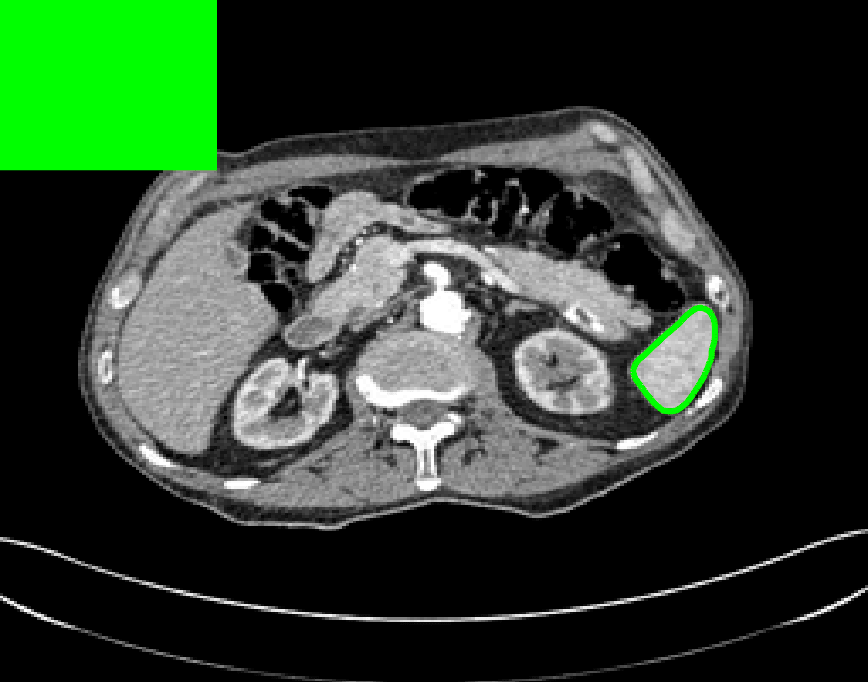

The motivation for this work comes from observing contradictions in using piecewise-constant intensity fitting terms in selective segmentation. Whilst good results are possible with this approach, the exceptional cases lead to severe limitations in practice. This is quite common in medical imaging as demonstrated in Fig. 1, where the target foreground has a low intensity. Given that the corresponding background includes large regions of low intensity, the optimal average intensities for this segmentation problem are and . For cases where , we see that by (1), almost everywhere in the domain . This means that it is very difficult to achieve an adequate result, without an over-reliance on the user input or parameter selection.

3.2 Submarkov Random Walks (SRW) SRW

We now introduce a recent selective segmentation method by Dong et al. SRW known as Submarkov Random Walks (SRW). Rather than using the continuous framework of Chan:06 , this approach is based in the discrete setting where each pixel in the image is treated as a node in a weighted graph. Random walks (RW) have been widely used for segmentation since the work of Grady RW . SRW is capable of achieving impressive results with user-defined foreground and background regions. The selective segmentation result can be obtained by assigning a label to each pixel based on the computed probabilities of the random walk approach. For brevity, we do not provide the full details of the method here, however, further details can be found in SRW . We compare SRW to our proposed approach on a CT data set in §7.4.

Test Images. We will perform initial tests on the images shown in Figs. 5–7. We have provided the ground truth and initialisation used for each image. Test Images 1–3 are synthetic, Test Image 4 is an MRI scan of a knee, Test Images 5–6 are abdominal CT scans, and Test Images 7–9 are lung CT scans. They have been selected to present challenges relevant to the discussion in §2. We focus on medical images as this is the application of most interest to our work. In the following we will discuss the results in terms of synthetic images (1–3) and real images (4–9). We also test the proposed approach on a larger data set of 30 CT images (a sample of which is presented in Fig. 18), comparing against existing selective methods detailed in §3.

Real Images. In Fig 12 we present results for Test Images 4–6. Here, the proposed model performs in a similar way to its competitors because these images are more typical selective segmentation problems in the sense that there is a clear distinction between the foreground and background intensities. In particular, the values in each case are: Test Image 4 , Test Image 5 , and Test Image 6 . It can be seen that the proposed model is competitive compared to previous approaches. The performance is quite poor for Test Image 5, but is arguably still the best for this challenging case. In Fig. 13 we present results for Test Images 7–9. Here the proposed model outperforms previous approaches significantly for each image. This is mainly due to the type of image considered. Specifically, the true intensities are: Test Image 7 , Test Image 8 , and Test Image 9 . The proposed model is capable of achieving results where , with other models failing completely in these cases.

Real Images. In Table 1 we can see that the proposed model is the most successful in terms of optimal accuracy. It is worth noting some inconsistency in the other models, with all but GAV having results that fall below TC for at least one image. GAV performs well for Test Images 4–9, with the proposed model slightly outperforming it in each case. It is worth reminding the reader that for GAV the parameters have been refined for each example. Fixing this results in more variability in the quality of results. The proposed model has no such parameter optimisation between examples. CAC and SRW perform reasonably well for these images, although are sometimes substandard for Test Images 4-7. This is despite extensive refinement of the user input to achieve an acceptable result. We present the optimal results for Test Image 9 in Fig. 14. Here we can see how much variation there is in the quality of results for this lung CT image. CAC and SRW are competitive in this instance. Of the remaining approaches GAV is the most competitive (TC ), but is visually inadequate. Two other models (CV, HYB) fail completely. In this case, the problem looks quite straightforward and yet other fitting terms are insufficient to produce a good result. Again, the proposed model tends to be superior in cases where and is capable of achieving very good results for all the images considered. This highlight the advantages of the proposed fitting term.

7.4 Alternative Selective Methods

In order to further establish the robustness of our method, we now introduce the results of testing our approach against competing interactive segmentation methods on a larger data set. The results are presented in Fig. 17, showing a boxplot of accuracy in terms of TC on a set of 30 CT images (excluding outliers). The target structure we consider is the spleen, as this consists of a relatively homogeneous foreground, appropriate for the approach considered. The data has been manually contoured providing ground truth data for the image set. We compare CAC Nguyen:12 and SRW SRW against our method with five variations of user input for each image. It is worth emphasising here that the input used in the tests is identical for each approach and was not refined in any way. It was designed to mimic what a user, unfamiliar with each approach, might select intuitively. A representative example for three images is shown in Fig. 18. This shows foreground (red) and background (blue) user input regions. For our method, we define the red region as as discussed in §1 and enforce hard constraints on the blue region. We refer to the results of the proposed approach using this input as Ours (i). We also include results of randomising the user input in an identical way to §7.3. For each image we generate 1000 simulated user input choices, which we present as Ours (ii). It is important to note that the difference between Ours (i) and (ii) is only the definition of . The method and parameters are fixed between each.

The performance of CAC Nguyen:12 is very good, as shown in Fig. 17. We have included an additional figure to highlight the difference between CAC and Ours (i) and (ii) more precisely. This is shown in Fig. 19 (this is the same as Fig. 17 with TC restricted to [0.8,1]). Here we can see that the proposed approach has a slightly better median (0.96 compared to 0.94) and is generally more consistent than CAC. This is particularly evident when considering the worst TC results of CAC () against ours ().

In Fig. 17 it can be seen that our method exceeds the performance of SRW by a large margin (0.66 compared to 0.95). One possible reason for this is that the input used, as displayed in Fig. 18, is restricted to be as intuitive as possible. SRW is capable of achieving improved results with more elaborate foreground/background input. However, it is generally reliant on a trial and error approach which is not ideal in practice. This highlights an important advantage of our method. It is able to achieve a high standard of results with simple user input. This is reinforced by considering Ours (ii), where the results of 30000 random variations of the user input does not cause a drop off in accuracy compared to the 150 manual user input selections. Again, this can be seen more clearly in Fig. 19. In fact, the results for the proposed approach with the random input are slightly better than with the manual input. This underlines the robustness to user input in the model, which is a vital aspect of selective segmentation.